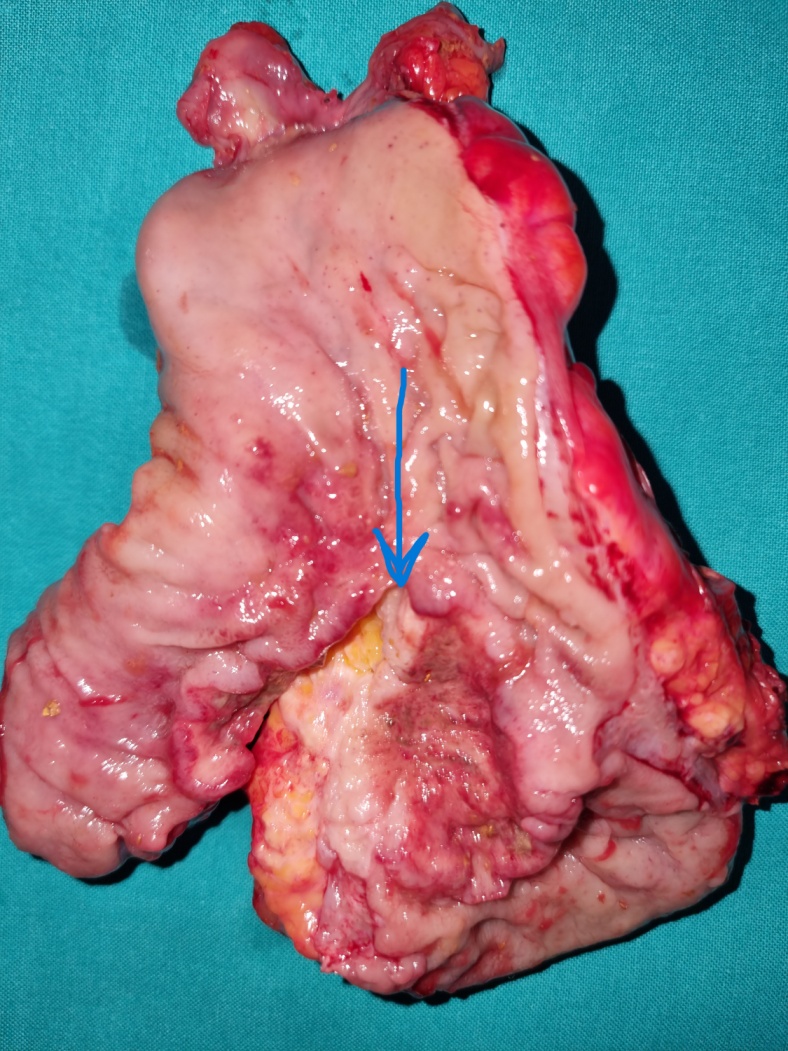

Low anterior resection of the rectum – Total mesorectal excision (Courtesy Dr. V. Penopoulos)